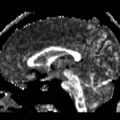

File:Unc fornROI.png

Unc_fornROI.png (512 × 512 pixels, file size: 130 KB, MIME type: image/png)

| current | 14:10, 27 July 2007 | 512 × 512 (130 KB) | Kubicki (talk | contribs) |